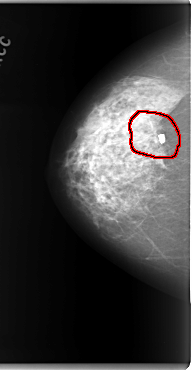

C_0085_1.RIGHT_MLO

FILE: C_0085_1.RIGHT_MLO.OVERLAY

TOTAL_ABNORMALITIES 1

ABNORMALITY 1

LESION_TYPE MASS SHAPE IRREGULAR MARGINS SPICULATED

ASSESSMENT 5

SUBTLETY 4

PATHOLOGY MALIGNANT

TOTAL_OUTLINES 1

BOUNDARY